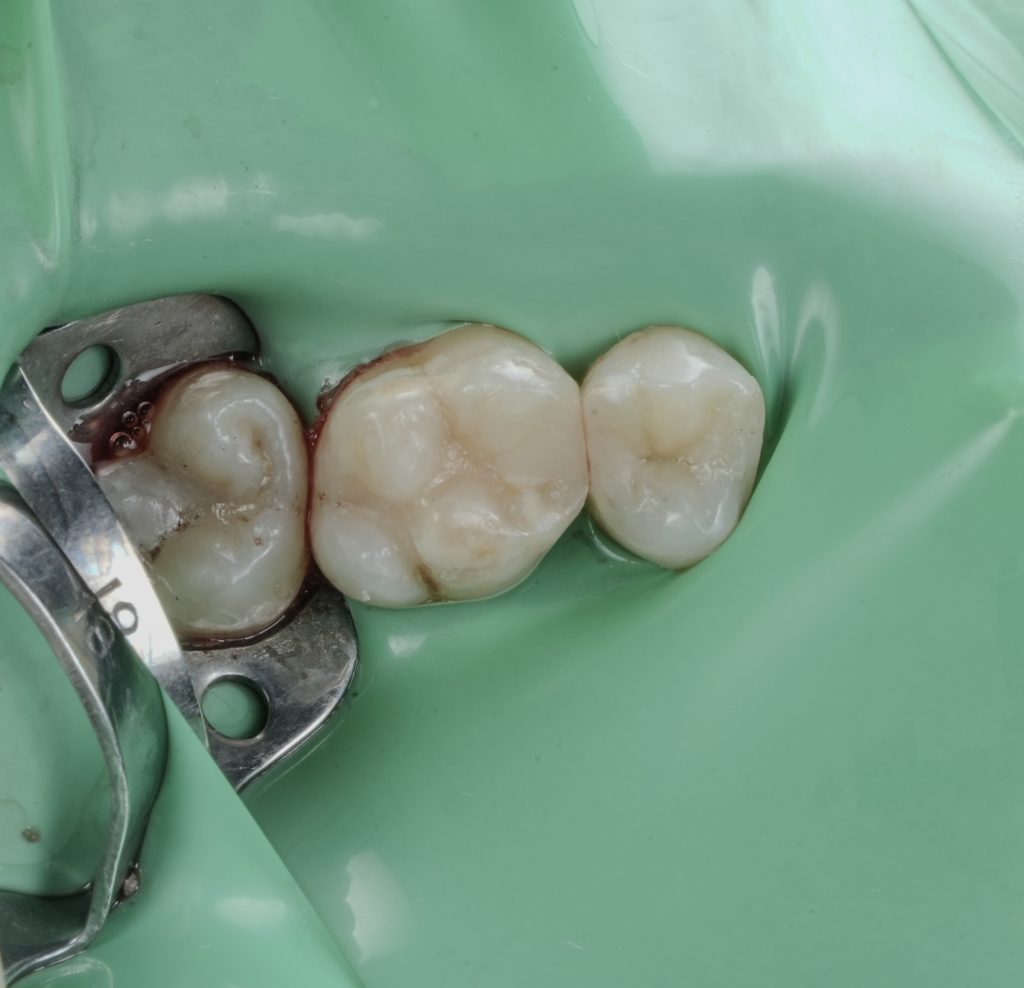

Images to place

- Fig. 12: Immediate post-op occlusal (dam still on).

- Fig. 13: Post-op occlusal after polish (dam off).